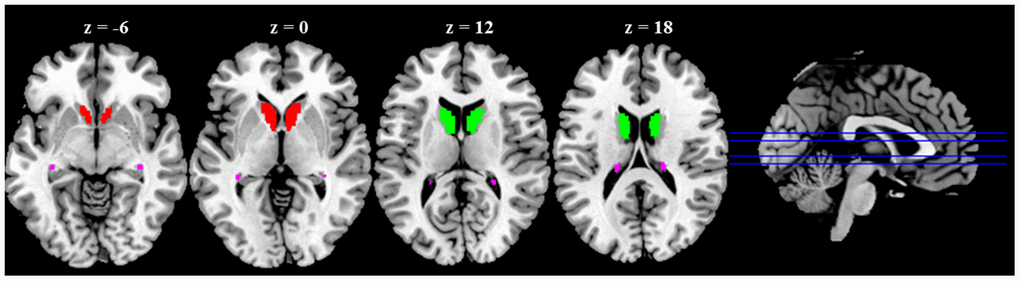

Rs-fMRI data were preprocessed using SPM12. Seed-to-voxel correlation analysis was carried out by Data Processing and Analysis for (Resting-State) Brain Imaging (DPABI) V4.3 [23]. The first ten functional images were discarded to minimize the fluctuation of the MRI signal in the initial stage of scanning. The remaining 190 images of each subject were first corrected for slice timing to reduce the within-scan acquisition time differences between slices and then realigned to eliminate the influence of head motion during the experiment. All subjects included in the present study exhibited head motion less than 1.5 mm in any of the x, y, or z directions and less than 1.5° of any angular dimensions. Next, the realigned images were co-registered to T1 images, spatially normalized into MNI space using transformations from segmentation, and resampled voxel size into 3 × 3 × 3 mm3. Subsequently, the functional images were smoothed with a 4-mm FWHM isotropic Gaussian kernel. After preprocessing, images were then band-pass filtered to 0.008 ~ 0.09 Hz to reduce noise. Further denoising steps included regression of six motion parameters and their first-order derivatives, regression of WM and CSF signals following the CompCor strategy [24] and a linear detrending. The seed-regions of the bilateral caudate head, body, and tail were defined based on WFU_PickAtlas [25] (Figure 4). The correlation coefficients between the seed voxels and all other brain voxels were computed to generate correlation maps. For group analyses, the correlation coefficients were converted to z-value using Fisher's r-to-z transformation [26].